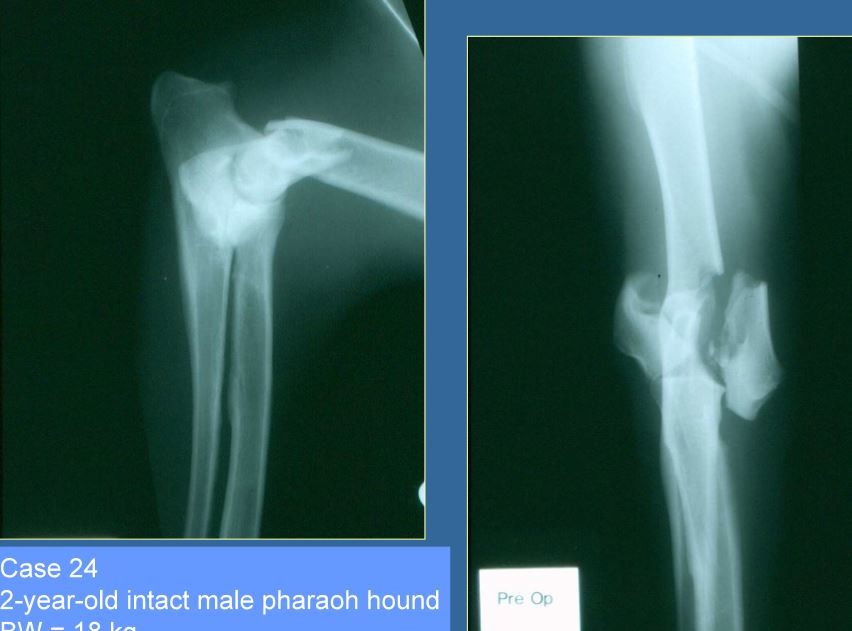

2 year old M Pharaoh hound, 18kg

Classify and assess fracture, and give repair options

Comminuted T or Y fracture

Fx score= 3-5

Repair: Osteotomy of olecranon, bilateral plates or pins